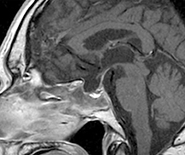

ところが、最近少しずつ状況が好転してきました。平成18年、欧米を始め世界各国ではすでに悪性神経膠腫の標準薬として使用されていたテモゾロミドが、我が国でも承認されました。この抗癌剤は飲み薬ですが従来の注射薬と比べても治療効果が高く、2年生存率を3倍に伸ばすという効果が実証されています。図1の患者さんは、手術・放射線や他の薬剤を使用した化学療法でも腫瘍の進行を全く止めることが出来なかったのですが、テモゾロミドを4コース使用した後に、腫瘍が完全に消失しました。この患者さんはその後3年間にわたって再発がありません。

図1:悪性脳腫瘍に対するデモゾロミドの効果

投与前

4コース終了後